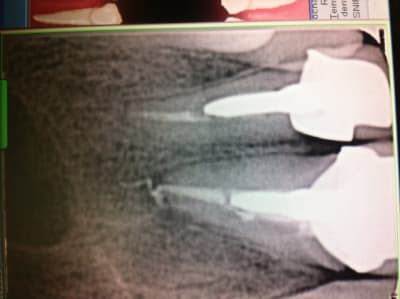

Ras à la rétro sauf un petit dépassement sur 21. Gencive tuméfiée, violacée en vestibulaire de 21-22. La 21 a déjà eu un Rte il y a 4 ans.

Rien au sondage, mais en regardant de plus prés la rétro, je suspecte un trait de fracture en distal de 22...

Mis sous Antibio, plus de signe clinique. Prescription de cone Beam et surprise, belle image...

Que penses tu de la taille de la lésion?

Elle est quand même volumineuse. Tu penses qu'en greffe d'apposition pourrait être envisageable?